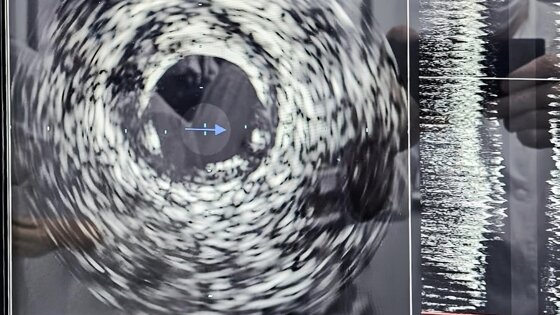

В отделении рентгенэндоваскулярной диагностики и лечения КОКБ проведены первые успешные операции на сосудах сердца с использованием новой технологии – внутрисосудистого ультразвукового исследования (ВСУЗИ).

Как рассказал заведующий отделением Евгений Перевалов, исследование проводится специальным ультразвуковым датчиком диаметром около 1 мм.

Датчик вводится в артерию и позволяет хирургам за 5-7 минут получить важную информацию о составе атеросклеротической бляшки, степени сужения артерии и других параметрах, – сообщил специалист. – Методика позволяет измерить диаметр артерии с точностью до 0,1 мм, выбрать идеально подходящий коронарный стент и оценить восстановление кровотока. Аппарат ВСУЗИ также оснащен функцией исследования физиологической оценки кровотока для более точного определения тактики лечения.